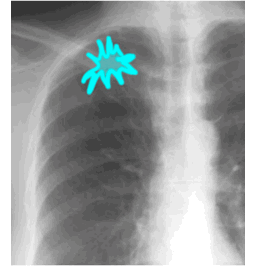

C

SHAPE - irregular

MARGIN - spiculated

SIZE - 4 cm

DENSITY - soft tissue

NOTE: any spiculated lung opacity of amy size must be called a 'MASS'